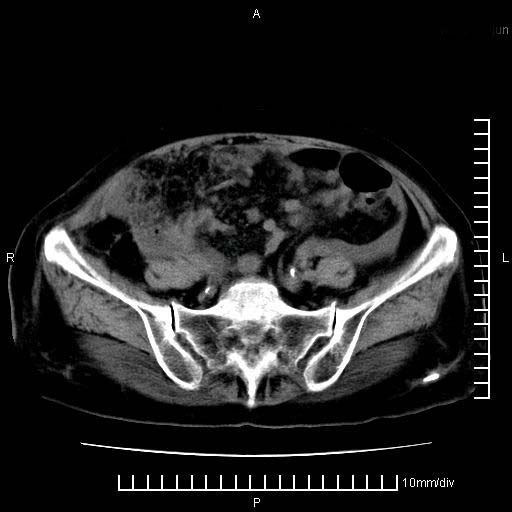

标题: CT28280:腹部增强:女性,80岁

上腹疼痛月余,外院核磁诊断胰腺癌。现临床示右下腹可明显触及包块,可片子上怎么没有看到?

胰腺体部癌累及周围器官,腹膜、粘连,临床摸到的可能是粘的组织

胰腺结构模糊,胰尾部见囊性包块,周围脂肪密度增高,左肾前筋膜增厚,胸水、腹水。不符合胰腺ca伴腹膜腔转移。考虑胰腺炎伴假性囊肿形成、胸腹腔积液。

1)考虑胰腺癌并胰腺假性囊肿形成。2)肝内低密度灶,不排除转移。3)右肾盂积水。4)腹水。5)右侧胸腔积液并右肺下叶部分膨胀不全。